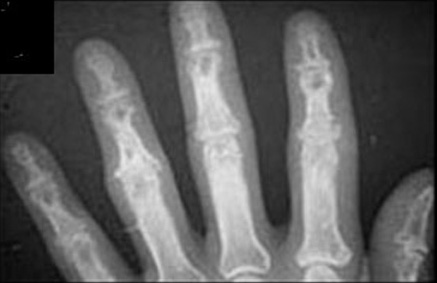

Sarcoidosis

Punched out lesions in bone